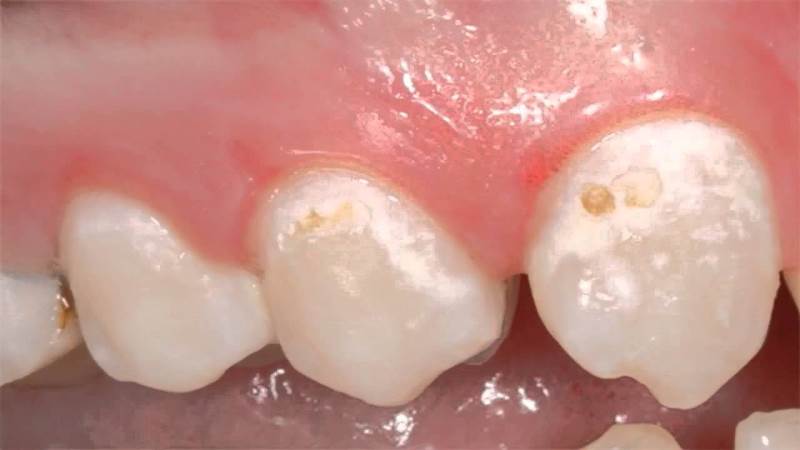

При кариесе сначала появляются белые пятна. Лечение может проводиться без применения бормашины с помощью реминерализации и фторирования. При поражении эмали она становится мягкой и шершавой, и если не начать лечение, пятна становятся темнее и проникают вглубь, переходя в следующую стадию кариеса. Часто пятна образуются на пришеечной и боковой поверхностях.

Гипоплазия — это врожденный дефект, который может вызываться проблемами в период эмбрионального развития. Это состояние может быть обусловлено токсикозами во время беременности матери, а также родовыми травмами и инфекциями. Если у ребенка появляется белое пятно на зубе, причиной может быть нарушение обменных процессов или недоразвитие. В молочном периоде пятна обычно появляются на передних зубах ребенка. Имея гипоплазию, зубы становятся уязвимыми, поэтому требуются защитные процедуры с использованием специальных средств. Стоматолог может определить возраст нарушения эмали по месту положения пятен.

Белые оттенки на зубах ребенка могут иметь желтоватый или коричневатый цвет. Они могут появляться из-за различных факторов, таких как развитие кариеса, недостаточная гигиена полости рта, гипоплазия, употребление кислотной пищи, системные заболевания, травмы зубов, насыщение организма фтором и различные отклонения в развитии ребенка. Гипоплазия может проявляться в виде полос, затемнений или поражений одного или нескольких зубов. Ортодонтическое лечение также может быть причиной поражений, когда скобы предотвращают контакт зубной части с слюной, что препятствует минерализации. Важно обратиться к стоматологу, чтобы установить причину и своевременно устранить проблему. Молочные зубы с белыми пятнами также следует сохранить до появления постоянных зубов. Диагноз может быть сложным, но опытный стоматолог может определить время протекания патологии и факторы раздражения. Также важно уделить внимание иммунной системе ребенка. Появление белых пятен после инфекционных заболеваний, перенесенных зимой, наблюдается у многих детей. Поэтому рекомендуется проводить закаливающие процедуры, заниматься спортом и проводить время на свежем воздухе. Стоматолог учитывает информацию о болезнях матери во время беременности при диагностировании белых пятен на молочных зубах ребенка.